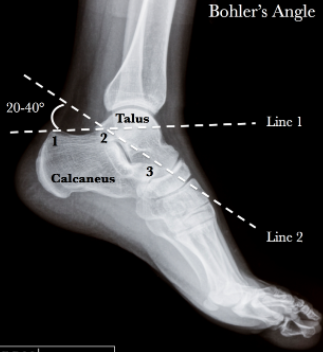

A) Le calcanéus est au-dessous du talus